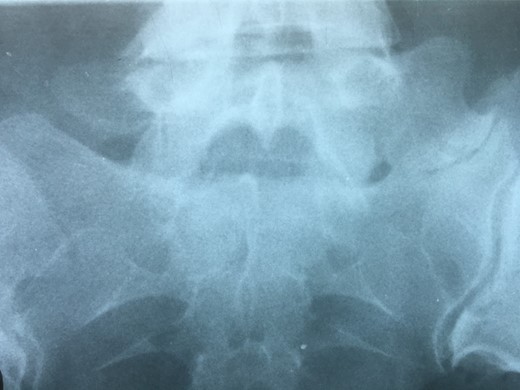

Degenerative changes at the facets and disc in the adjacent segment.